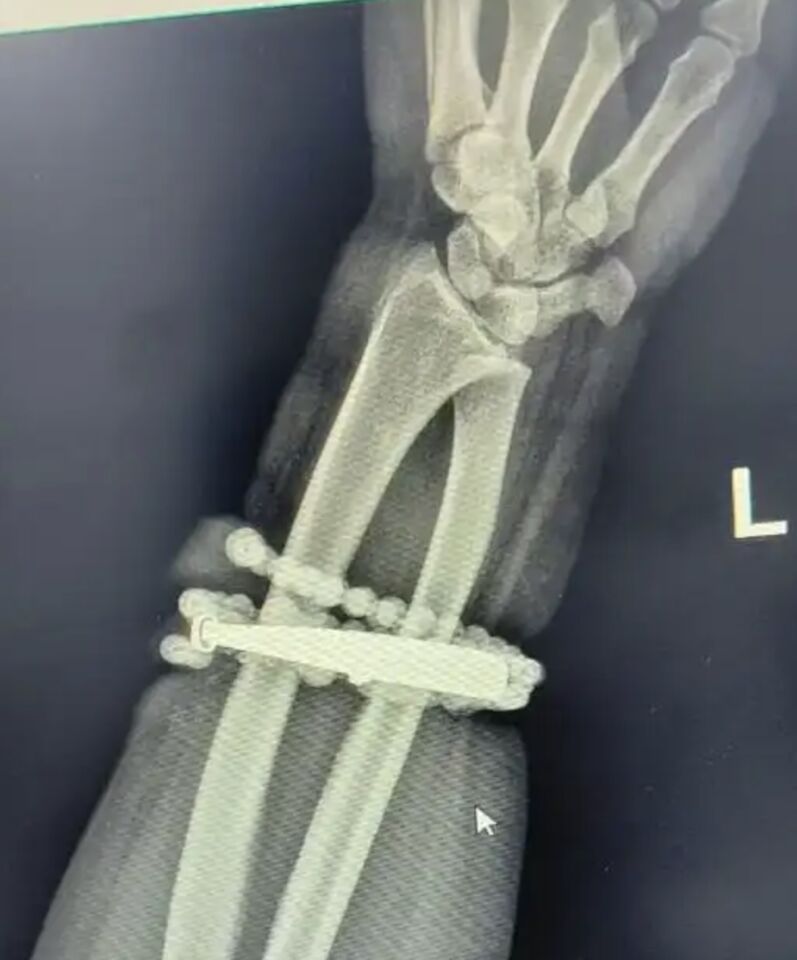

福建寧德33歲的龔姓女子手腕上的手鐲戴了將近10年都沒摘下來,隨著她逐漸變胖,手鐲最近越來越緊,甚至嵌入肉中,難以取下。龔女直到劇痛難耐才終於就醫,但手腕已經嚴重感染,必須進行手術。